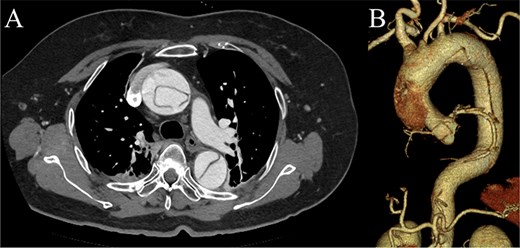

Preoperative contrast-enhanced CT images. (A) Stanford type A acute aortic dissection with the primary entry tear extending from the ascending aorta to the aortic arch, showing a patent false lumen. (B) Three-dimensional reconstructed image.

A 70-year-old woman presented to the emergency department with sudden-onset chest and back pain. Contrast-enhanced CT revealed an ATAAD extending from the ascending aorta to the bilateral common iliac arteries. The primary entry tear extended from the ascending aorta into the aortic arch, and the false lumen remained patent throughout its entire peripheral extent (Fig. 1). Both renal arteries originated from the true lumen, and there was no malperfusion. Vital signs were stable, and the patient was not in shock. The patient underwent emergency total arch replacement with FET implantation using a 27 × 90 mm FROZENIX four-branched graft (Japan Lifeline Co., Ltd, Tokyo, Japan). The procedure was completed in 7 h and 6 min without intraoperative complications. Postoperatively, urine output declined markedly. Serum creatinine increased from a baseline of 0.81 to 2.61 mg/dl on postoperative Day 1. Diuretics failed to improve urine output, and renal replacement therapy was initiated. Contrast-enhanced CT on postoperative Day 2 showed no signs of renal malperfusion. Although the renal medulla exhibited normal enhancement, a diffuse non-enhancing area throughout the renal cortex—referred to as the “reverse rim sign”—was observed, consistent with RCN (Fig. 2). Thrombosis of the false lumen in the descending thoracic and thoracoabdominal aorta had progressed (Fig. 3). The patient developed persistent coagulopathy, with sustained hypofibrinogenemia and thrombocytopenia. On postoperative Day 2, the platelet count was 4.1 × 104/μl, D-dimer 13.5 μg/ml, and PT-INR 1.54, yielding an International Society on Thrombosis and Hemostasis DIC score of 6, consistent with overt DIC. Anticoagulation therapy with heparin and warfarin was administered. Ultimately, by postoperative Day 50, a total of 36 units of fresh frozen plasma and 100 units of platelets had been transfused; however, coagulation parameters gradually normalized thereafter, and no further transfusions were required (Fig. 4). A follow-up CT on postoperative Day 21 demonstrated further remodeling of the thrombosed false lumen. Brain magnetic resonance imaging performed on postoperative Day 9 to investigate delayed emergence revealed multiple scattered small acute ischemic infarctions involving the cerebellum, brainstem, and cerebral cortex (Fig. 5). These were not attributed to large-vessel occlusion but rather to systemic microthrombotic emboli. Despite supportive care, renal function did not recover, and maintenance dialysis was initiated. The patient was transferred to another hospital on postoperative Day 182.